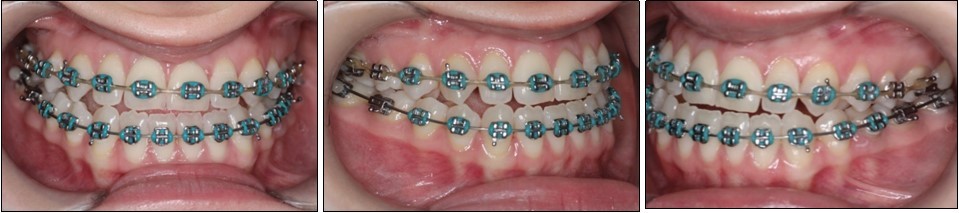

The pre-surgical orthodontic preparation successfully met the following objectives: levelling and aligning, flattening of curbe of Spee, proclination of the lower incisors and elimination of dental compensations. Before surgery, the patient had a normal position of the lower incisors, with IMPA 88 degrees. (Figure 4) Before surgery, a slight anterior open bite and an anterior crossbite could be observed, due to the elimination of dental compensations. Crimpable hooks were placed between each tooth on the 0.019x0.025 SS archwires, to allow placement of intermaxillary elastics after surgery. (Figure 5).

Figure 4.Pre-surgical extraoral photographs, after orthodontic preparation and preoperative lateral cephalometric radiograph

Figure 5.Pre-surgical intraoral photographs